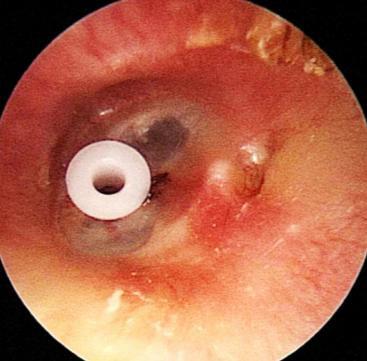

中耳通氣管為置放在耳膜上, 建立一個中耳腔與外界交通 的人工通道;使中耳內的積水 能流出,並可代替人體原有 耳咽管之通氣功能。